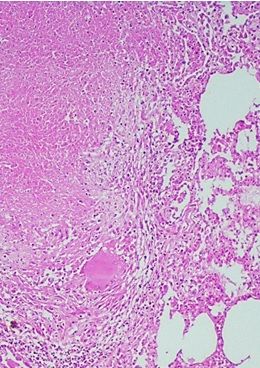

NECROSIS CASEOSA

ETIOLOGIA

- Se debe principalmente a infecciones persistente por microorganismos

se produce sobre todo en los focos de infeccion tuberculosa

Nivel macroscopico

tejido blanquesino y blando

nivel microscopico

celulas lisadas y un resto granular amorfo rodeados de un margen inflamatorio

foco de inflamacion es conocido como granuloma